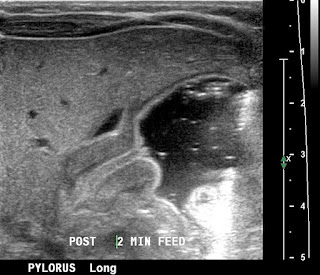

Ecografía:

Mediante ecografía puede verse el músculo hipertrofiado hipoecoico, con la mucosa central hiperecoica.

Engrosamiento del músculo del píloro >3 mm; longitud del píloro >15 mm.

Signos ecográficos:

- Donut o diana: músculo hipertrofiado hipoecoico rodeando a la mucosa hiperecoica.

- Signo del cérvix: indentación del píloro hacia el antro gástrico.

- Signo del pezón antral: mucosa redundante protuyendo en el antro gástrico.